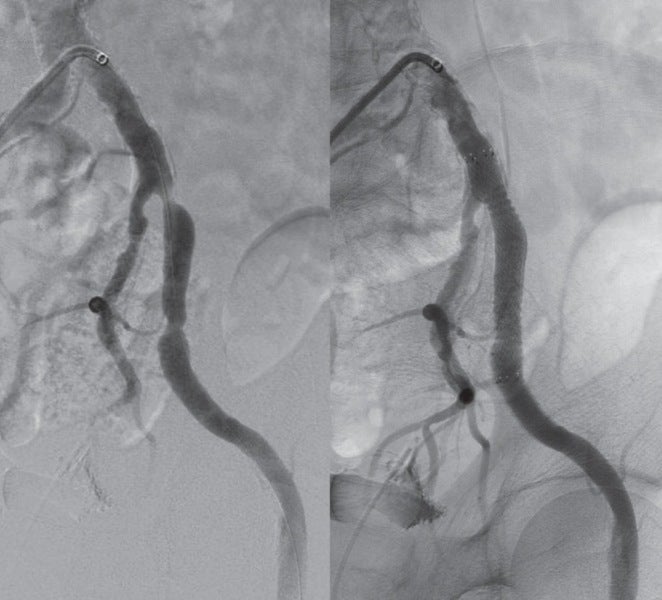

対側CFAより6 Fr 45 cm長のガイディングシースを挿入し山越えにて左EIA遠位部に進めた。この時点で圧波形は問題なかったため、手技を継続することとした。まず、5.5 Fr 100 cm長のガイディングカテーテルのバックアップ下、IVUSガイドに0.014 inchガイドワイヤー(先端荷重3 gポリマージャケットタイプ)を進めたところ、比較的容易にガイドワイヤー通過に成功した。IVUSでは全長にわたり intraplaqueを通過していたものの、血栓成分の多いプラークと考えられた。このため、5.5 FrのガイディングカテーテルをSFA遠位部に先進し、フィルターワイヤー(径 8 mm)を膝窩動脈に留置し遠位部保護を行った。続いて、5.5 Frガイディングカテーテルを用いて血栓吸引を行ったうえで、小径バルーン径 4.0 mm / 長 220 mmを使用し6 atmで前拡張した。(図3)この時点で造影にて末梢塞栓のないことを確認しフィルターワイヤーを回収、0.035 inchガイドワイヤーを用いて7 Fr 55 cm長のガイディングシースへ交換した。0.014 inchガイドワイヤー(先端荷重 1 g 親水性コートタイプ)を挿入後、SFA遠位よりバイアバーン® ステントグラフト径 7.0 mm / 長 150 mmを留置し、バルーン径 6.0 mm / 長 80 mmを用いてステントグラフト内のみ 18 atmで後拡張を行った。続いて、SFA近位部のlanding zoneをIVUSマーキングしたうえで、(図4)バイアバーン® ステントグラフト径 7.0 mm / 長 100 mmを追加留置した。先述のバルーン径 6.0 mm / 長 80 mmを用いて高圧拡張の後、近位部のみバルーン径 7.0 mm / 長 100 mmを使用し12 atmで後拡張を追加した。IVUSにてステントグラフトの拡張が良好かつmalpositionがないことを確認した。 最後に、EIAに対してベアメタルステント(BMS)径 10 mm / 長 60 mmを留置、後拡張を行って手技を終了した。(図5、6)

CTAではSFA起始部、遠位部ともにhealthy landingが可能と予想された。また、TASC分類C病変であり、良好な長期開存率を参考1、2にバイアバーン® ステントグラフトを使用する方針とした。Landing zoneについては、IVUSを用いhealthy intimaを同定、また可能な限り側副血行路を塞がないように留置することを心がけた。